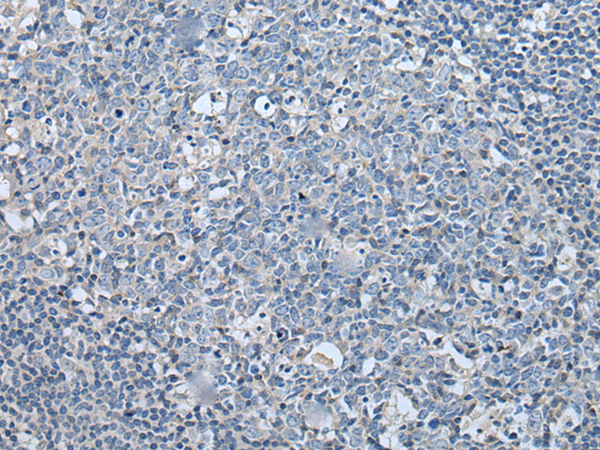

分类: 科研抗体货号: P02240别名: CIS; G18; SOCS; CIS-1; BACTS2应用: IHC反应种属: Human, Mouse, Rat